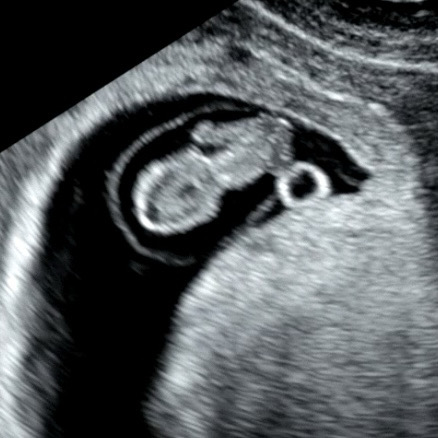

8주 0일차인데 젤리곰이..

잴리곰 보러 왔는데 젤리곰이 아니라 벌써 긴팔원숭이가 되어있는데 귀여운 젤리곰 모양은 어째 찍으신건지ㅠㅠ ㅋㅋㅋ

으핳핳 긴팔원숭이~~~ 넘 귀여워요 8주차 쪼꼬미네요 ㅠㅠㅠ 저도 다음주 8주차 곰돌이 보러 가는데 각도에 따라 또 달리 보일 수도 있겠어요☺️ 팔다리가 긴 멋진 아이가 태어나려나요 ㅎㅎㅎㅎ